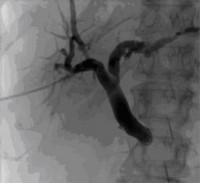

Percutaneous transhepatic cholangiography (PTCD) is a procedure in which bile is drained from the liver to the outside into a bag. It is used in cases of dilatation of the bile ducts (cholestasis) that cannot be drained into the intestine by ERCP (endoscopic retrograde cholangiopancreatography) for technical reasons (tumor that cannot be passed, Z.n. surgery).

Figure: External biliary drainage (PTCD) for biliary outflow obstruction due to pancreatic head tumor.